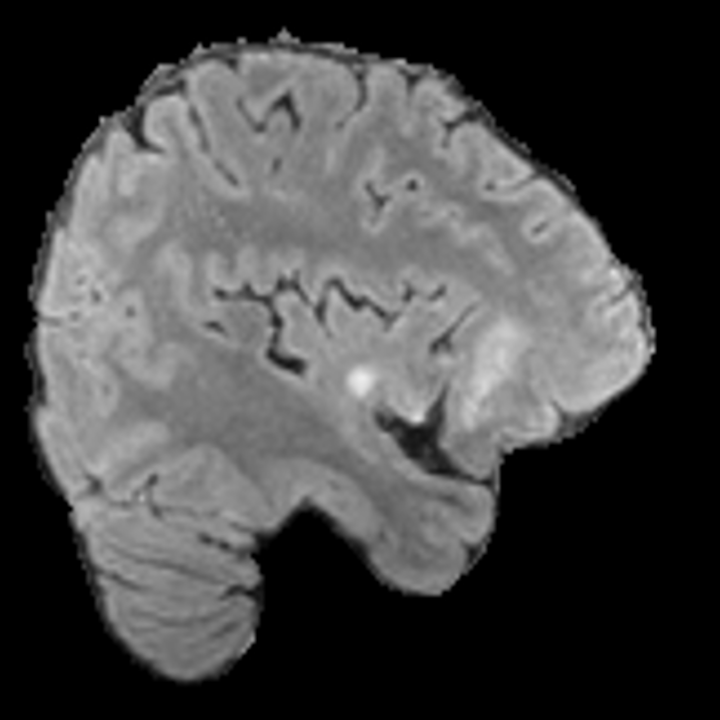

Tumour Information Preservation. For the brain tumor segmentation, we use a Swin UNETR model[28, 70], trained with random rotation, and intensity as data augmentation. On the test set with human ground-truth annotations (), the brain volumes generated from single slice input preserve the volume of the different tumour components (paired t-test, for all 3 classes). In Figure 4, we highlight the tumor profiles of the generated MRIs compared to the ground truth tumour profile. The real MRI Dice score in the test set is 85.15 while the generated MRIs from a single slice have a dice score of 83.09. This shows how the generated MRIs indeed preserve the tumor information and can act as an affordable and informative pseudo-MRI, before conducting an actual costly MRI examination in hospitals. More detailed results are provided in supplementary material.

Leveraging Context. Since we train on a predominantly cancerous brain dataset, one question that might arise is whether X-Diffusion generated MRIs preserve tumour information when the given inputs do not intersect with any tumour. We perform experiments varying the input slice index used to generate the 3D brain MRIs and measure the performance for input slices with no intersection with the tumour (not a single pixel with tumor label in the input slice). We also measure performance when only input slices are selected from tumor range. The Dice Scores of the random slices, no-tumour, and only-tumour are 83.09, 79.23, and 83.68 respectively. As can be seen here, the brain volumes generated from input slices with no tumour still preserve tumour information in reconstructed brain volumes despite a small drop in performance. This indicates that X-Diffusion is leveraging the context to preserve key information, such as tumor locations. This observation is consistent with how tumor segmentation models with global context [13] perform better than local-based U-Nets. More details are provided in supplementary material.